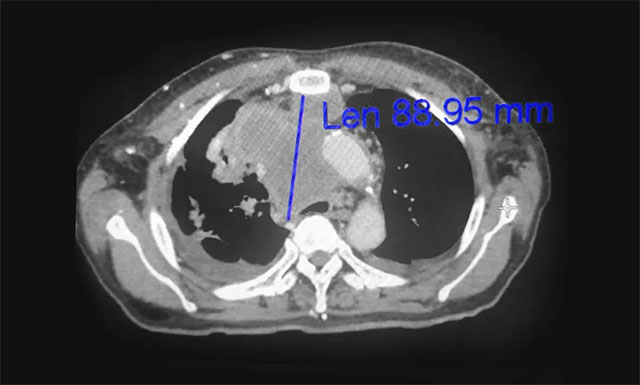

▲ 放療前

對于肺癌的治療方法,王曉東主任介紹說,其主要有:手術治療、化學治療、放射治療等綜合治療,才能取得比較好的效果。而卞先生的病灶位置不是很理想,所以治療時要特別注意。如今,卞先生有現(xiàn)在的治療效果已很不錯了。醫(yī)生治療是一方面,患者的心態(tài)也很重要!要有信心,才能有希望!